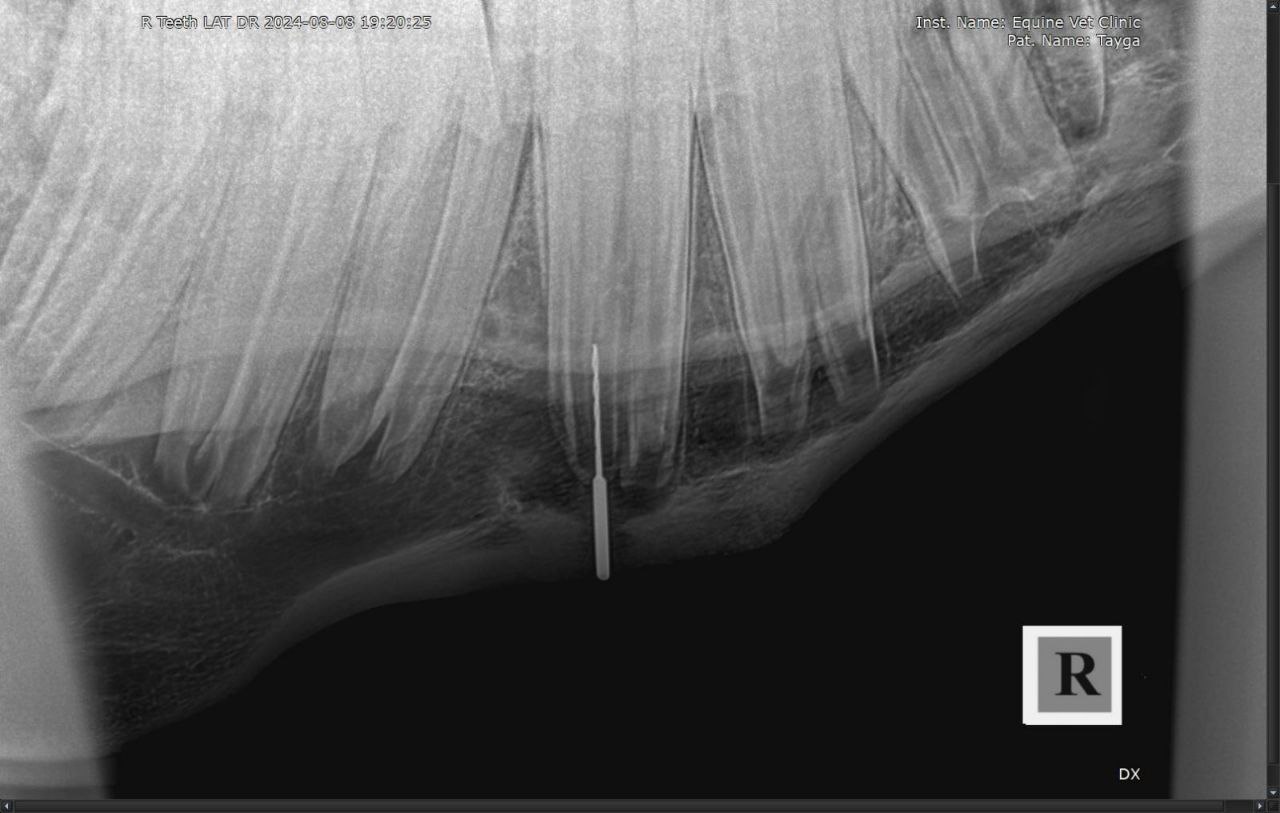

Результаты рентгенологического исследования: наблюдается неравномерная рентгенологическая плотность вокруг верхушки корня и утолщение кортикальной зоны кости нижней челюсти в проекции 408 зуба. Зондированием свища в нижней челюсти установлена вовлеченность корня 408 зуба в формировании канала свища.